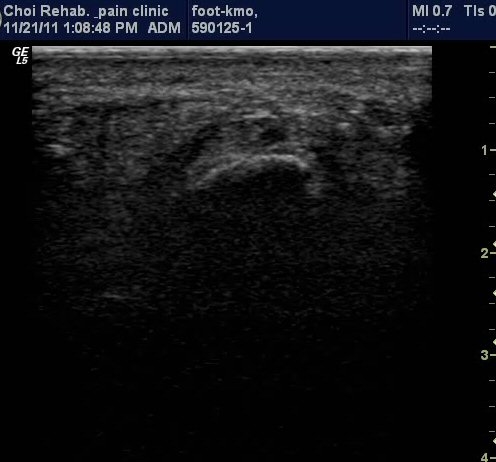

µÚ²ÞÄ¡ Á¾´Ü¸é°Ë»ç¿¡¼­ Á·Àú±Ù¸·ÀÇ Àú¿¡ÄÚ ºÎÁ¾ÀÌ ¶Ñ·ÈÇÔ(±×¸² 1, 2).

Ⱦ´Ü¸é°Ë»ç¿¡¼­µµ Á·Àú±Ù¸·ÀÇ Àú¿¡ÄÚ ºÎÁ¾ÀÌ ¶Ñ·ÈÇÔ(±×¸² 3).